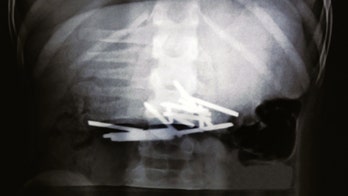

Boy recovering after swallowing 12 nails that punctured his organs A 10-year-old Chinese boy with an eating disorder is on the mend after surgeons removed 12 nails from his stomach that he had swallowed.